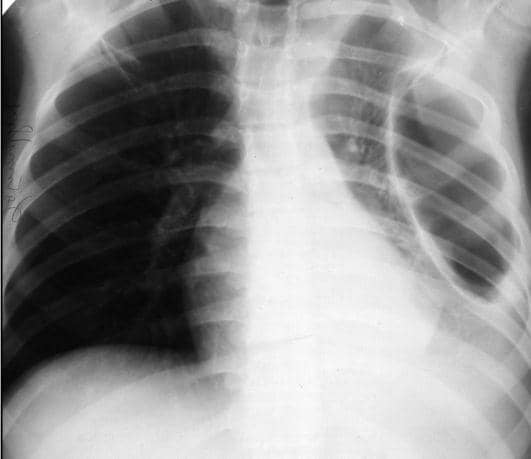

7. Pneumotoraks

Pneumotoraks adalah kondisi dimana terbentuknya sebuah kantong udara pada bagian paru-paru yang membuat paru-paru tersebut tertekan dan menjadi mengecil. Akibatnya anda anda akan kesulitan untuk bernapas secara penuh dan panjang karena ruang paru-paru yang kini terbatas.